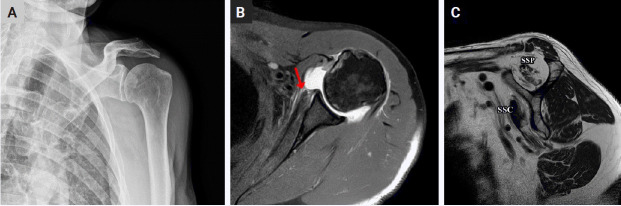

Abstract Image